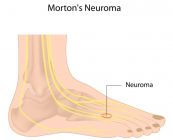

U dây thần kinh Morton là bệnh ảnh hưởng đến sự phì đại dây thần kinh của bàn chân và thường xảy ra ở khu vực giữa ngón chân thứ ba và thứ tư. Cùng eLib.VN tìm hiểu bài viết dưới đây để hiểu rõ hơn về bệnh lý này nhé!